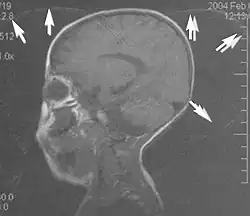

Flow

Flow can manifest as either an altered intravascular signal (flow enhancement or flow-related signal loss), or as flow-related artifacts (ghost images or spatial misregistration). Flow enhancement, also known as inflow effect, is caused by fully magnetised protons entering the imaged slice while the stationary protons have not fully regained their magnetization.[1] The fully magnetized protons yield a high signal in comparison with the rest of the surroundings. High velocity flow causes the protons entering the image to be removed from it by the time the 180-degree pulse is administered. The effect is that these protons do not contribute to the echo and are registered as a signal void or flow-related signal loss (Fig. 2).[1] Spatial misregistration manifests as displacement of an intravascular signal owing to position encoding of a voxel in the phase direction preceding frequency encoding by time TE/2.The intensity of the artifact is dependent on the signal intensity from the vessel, and is less apparent with increased TE.[1]